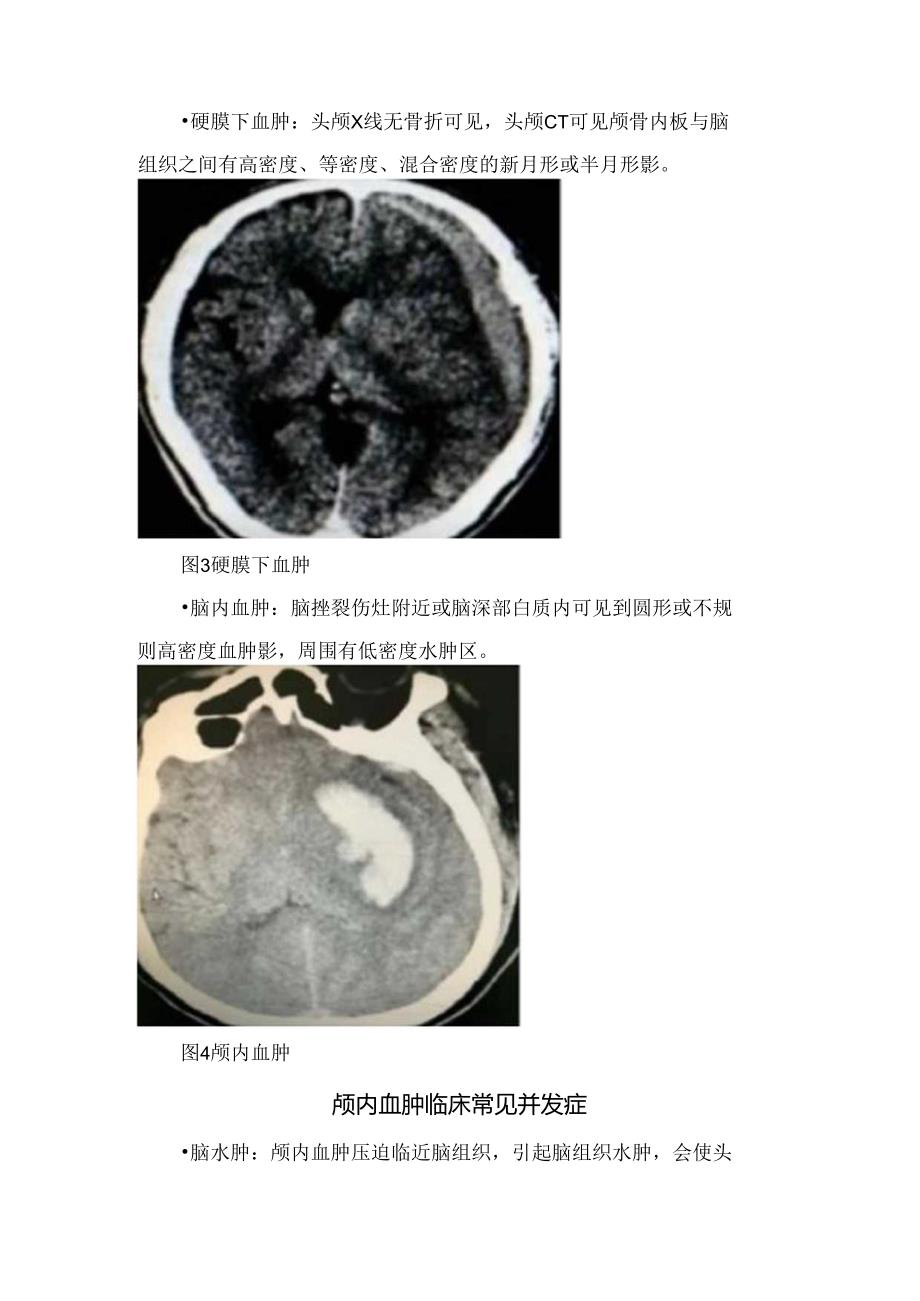

3、肿在脑组织内称脑内血肿。临床表现:脑内血肿以进行性加重的意识障碍为主,颅内压增高症状明显,若血肿累及重要脑功能区,可出现偏瘫、失语、癫痛等症状。根据血肿症状出现时间分类 急性血肿:伤后72小时以内出现症状者。亚急性血肿:伤后3日-3周内出现症状者。慢性血肿:伤后3周以上出现症状者。根据辅助检查分类硬膜外血肿:头颅X线平片可见骨折线,头颅CT可见颅骨内内板与脑表面间双凸形或梭形高密度影。图2硬膜外血肿硬膜下血肿:头颅X线无骨折可见,头颅CT可见颅骨内板与脑组织之间有高密度、等密度、混合密度的新月形或半月形影。图3硬膜下血肿脑内血肿:脑挫裂伤灶附近或脑深部白质内可见到圆形或不规则高密度血肿影,周围

4、有低密度水肿区。图4颅内血肿颅内血肿临床常见并发症脑水肿:颅内血肿压迫临近脑组织,引起脑组织水肿,会使头痛、恶心、呕吐等症状加剧。 脑疝:颅内血肿压迫脑脑干及小脑,引起脑疝,出现瞳孔变化、双侧瞳孔不等大、心率加快、血压不稳甚至危及生命。颅内血肿治疗原则 非手术治疗降低颅内压:20%什露醇改善脑循环、解除脑血管痉挛等:钙离子拮抗剂(尼莫地平)降低血管通透性、保护脑组织:糖皮质激素 手术治疗开颅血肿清除术去骨瓣减压术钻孔引流术:慢性硬膜下血肿脑室引流术钻孔探查术颅内血肿手术指征1 .有明显颅内压增高症状和体征。2 .CT扫描提示明显脑受压的硬膜外血肿。3 .小脑幕上血肿量30m1.、区血肿量20m1.、幕下血肿量:IOmI以及压迫大静脉窦而引起颅高压的血肿。4 .病人意识障碍进行性加重或出现昏迷。5 .在非手术治疗过程中病情恶化。